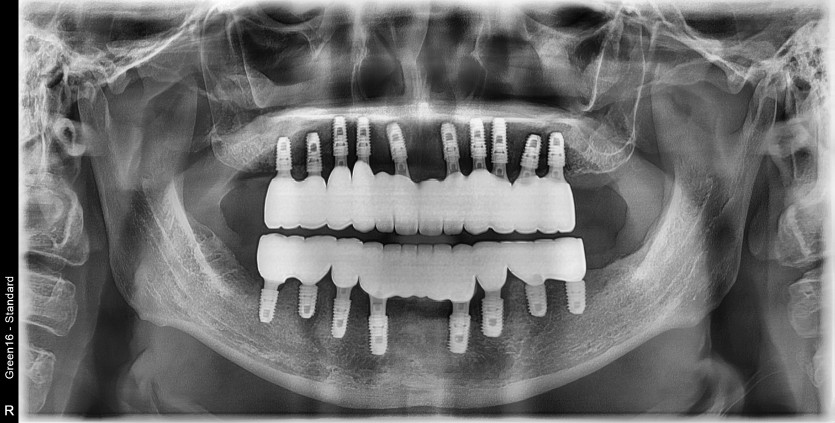

만 36세 전체 임플란트 증례

전체 임플란트 증례입니다.

18개의 임플란트로 완성하였습니다.